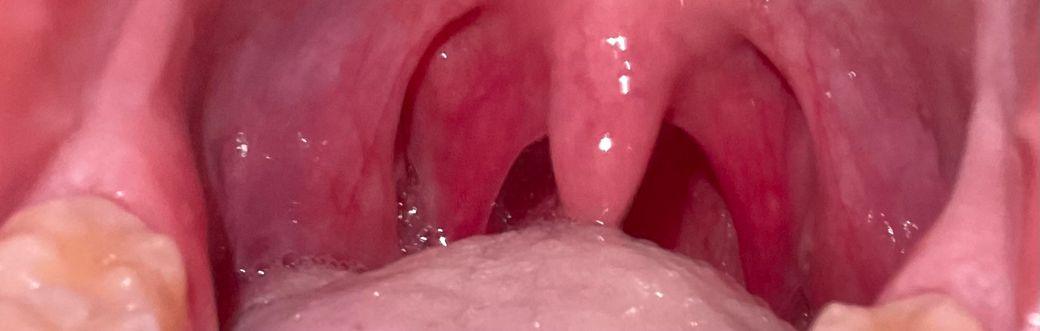

어제 밤부터 너무 아프길래.. 목상태 한번확인해주세요ㅜㅜ 제가 느끼기에 독감인 것 같긴한데 목이 너무 아파서요 ㅜㅜ 많이 부운 건가요???

• 1번 째 사진

올려주신 사진에서 편도는 확인되지 않으나 인두부의 발적이 보여 인후통이 심할 것으로 생각됩니다.

글쎄요 사진만 보아서는 심해보이지는 않습니다